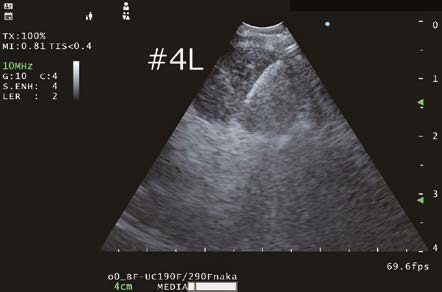

4L Lymph node observation

Obtaining improved B-mode images, which is the basis of all observation modes, will contribute the overall improvement of Endobronchial ultrasound-transbronchial needle aspiration (EBUS-TBNA) examinations. The EU-ME3 demonstrates improved ultrasound image resolution and depth compared to its predecessor, the EU-ME2. As a result, not only are the margins of the structure of interest more clearly delineated, but the texture of the lymph node cross-section can also be distinctly identified.